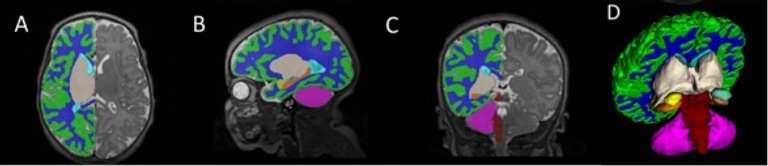

We prospectively recruited mother-baby dyads during the COVID-19 pandemic, who had been exposed to the SARS-CoV-2 virus during pregnancy (2020–2022) into a longitudinal infant brain development study and compared them to a low-risk normative pre-pandemic cohort (2016–2019). Quantitative 3-D volumetric magnetic resonance imaging (qMRI) was conducted at a neonatal visit when the infant was approximately 2 weeks of corrected age. Behavioral development was assessed using the Bayley Scales of Infant and Toddler Developmental, Third Edition (BSID-III) and the Infant-Toddler Social and Emotional Assessment (ITSEA), when the child was approximately 2 years old. An ordinary least squares regression model was used to determine the neurodevelopment of toddlers relative to their exposure to the SARS-CoV-2 virus. Mediation analyses were performed to assess how in utero exposure to SARS-CoV-2 affected the newborn brain and toddler developmental outcomes. Analyses were adjusted for maternal age and educational level, infant sex, and total brain volume on qMRI.